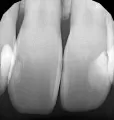

Я сама вижу, что через пломбы (на 7 зубе точно) просвечивается что-то темное. Прикладываю фото нынешнего состояния и снимок до установки пломб (на который поглядывал врач при пломбировании).

Скажите, пожалуйста, может ли это быть вторичный кариес? Или эта темнота под пломбой может быть и не кариесом, а чем-то другим? Что стоит спросить у врача, который ставил пломбы? Допустил ли он какую-то ошибку?

Вторичный кариес так мгновенно не развивается. Явно проглядываются остатки кариозной полости.